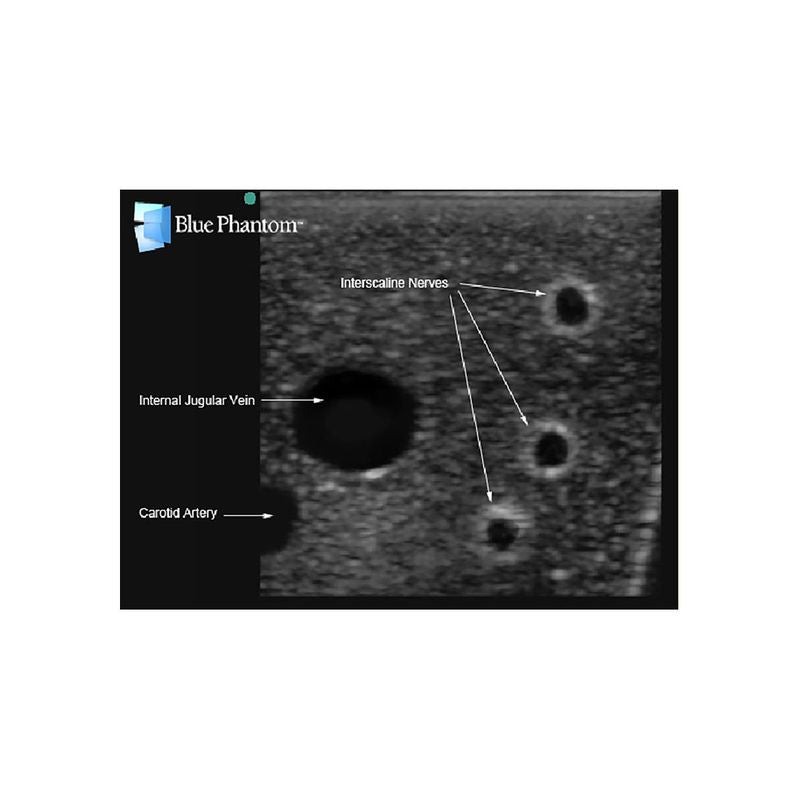

Replacement tissue insert for Central Line and Regional Anesthesia Model (BPHNB670 series).-